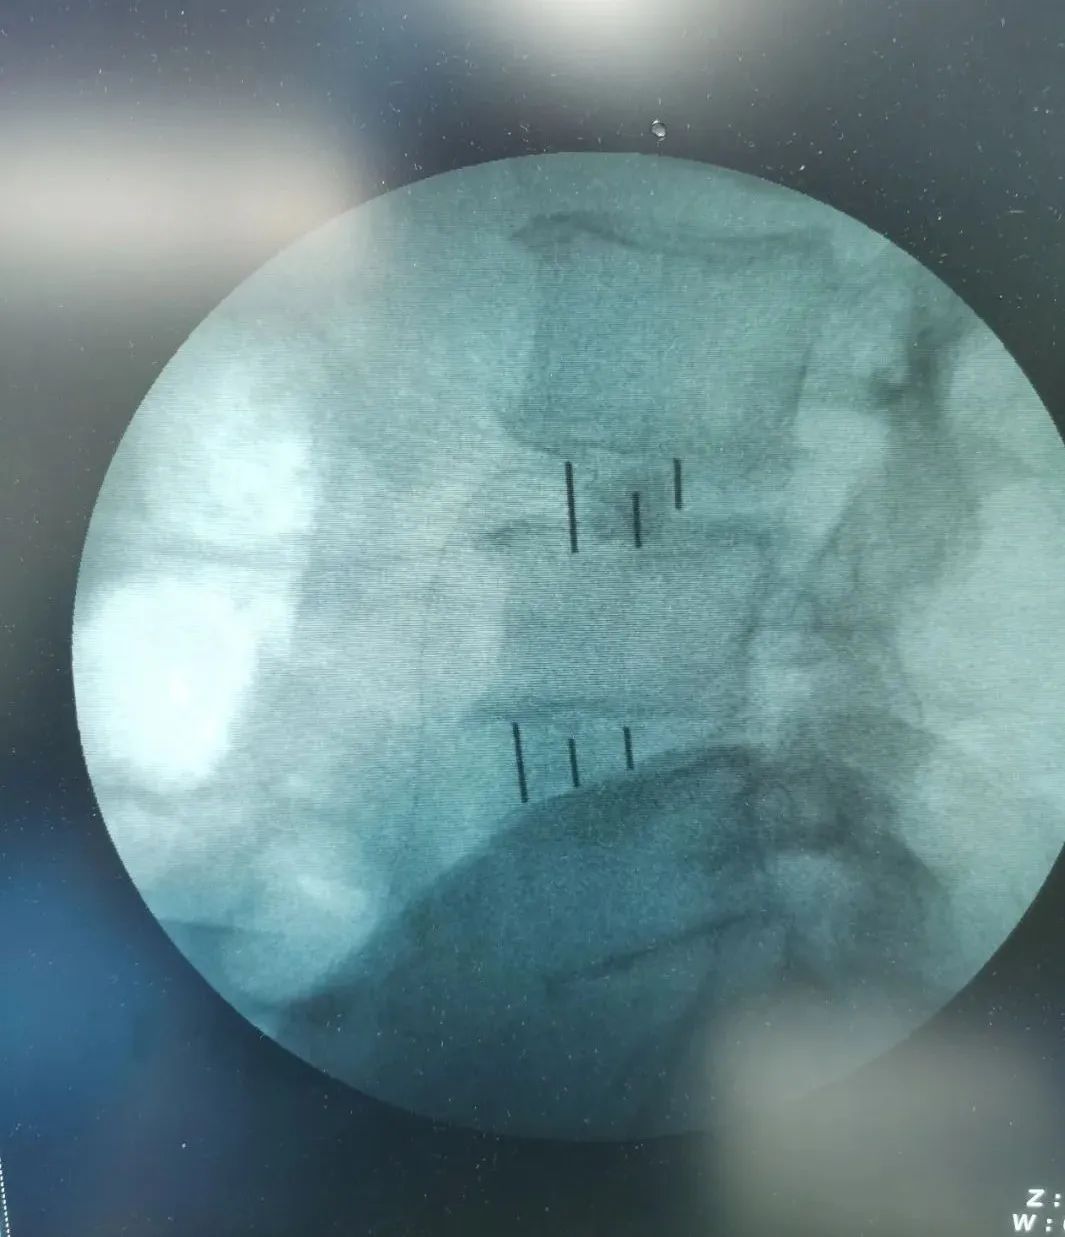

▲术中影像

经过周密细致地术前讨论及评估,由张少华主任主刀,熊东医生、手术室(麻醉科)默契配合,为李先生成功实施“OLIF腰椎微创椎体间融合术”,目的:减压,复位,融合;术中操作干净利落、精准微创,顺利完成,手术历时近4小时。